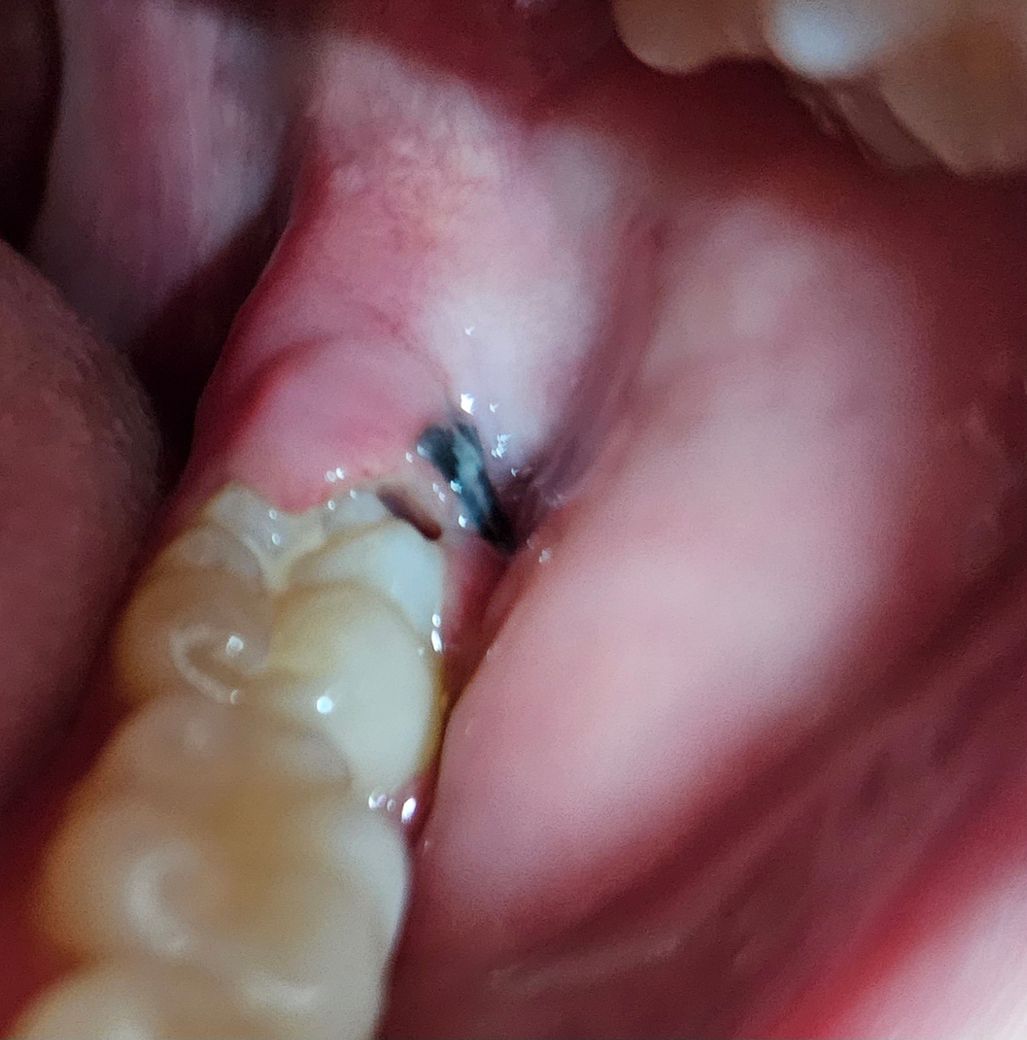

사랑니 발치 후 6일됐는데 잇몸이 너무 아파요

사랑니 목요일에 뽑았는데 아직도 이렇게 붓고 아파요.. 양치하기도 힘든데 정상일까요? 뽑고나서 일요일까지 얼굴 붓기도 엄청 심했습니다. 아직도 볼 부어있고 멍 들어있는 상태구요. 참고로 검은건 실밥이고, 구멍처럼 보이는 건 부은 잇몸과 이 사이의 공간입니다.. 잇몸이 너덜너덜 거리는 것 같아요.

사랑니 발치한곳에 음식물이 많이 껴서 그러시는거 같으니 실밥을 푸실떄 소독받으시면 괜찮아 지실꺼에요.

사진상으로는 붓기는 있어 보이나 크게 문제가 보이지는 않습니다. 통증이 너무심하면 치과를 가보시는 게 좋겠습니다.